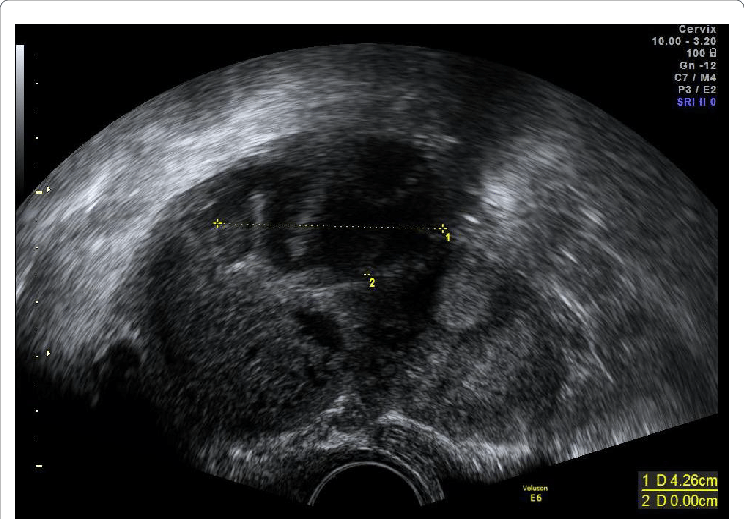

Which of the following represents the most likely diagnosis of ultrasound picture below ?

47.